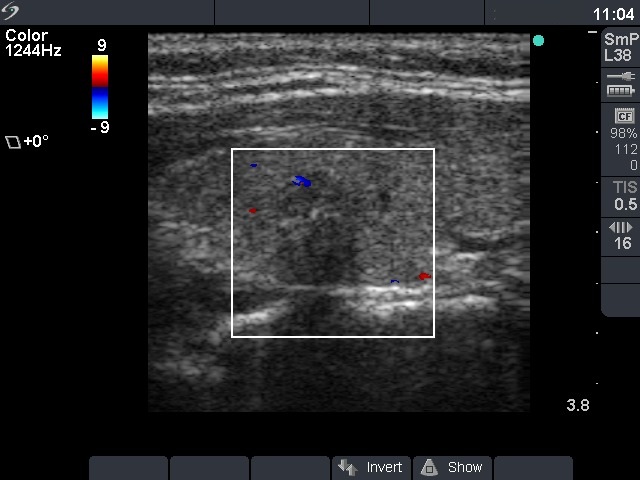

Ultrasonography: the thyroids were echonormal. There was a small moderately hypoechogenic lesion in the left lobe. The nodule displayed microcalcifications and had blurred borders.

The ultrasound pattern was suspicious for a papillary cancer. The combination of hypoechogenicity, irregular borders, the presence of microcalcifications and the taller-than-wide sign increased the risk of malignancy to more than 10-fold. In our minimally-moderately iodine deficient region, it means that instead of a 2.2% risk the patient had a 25% risk for malignancy.